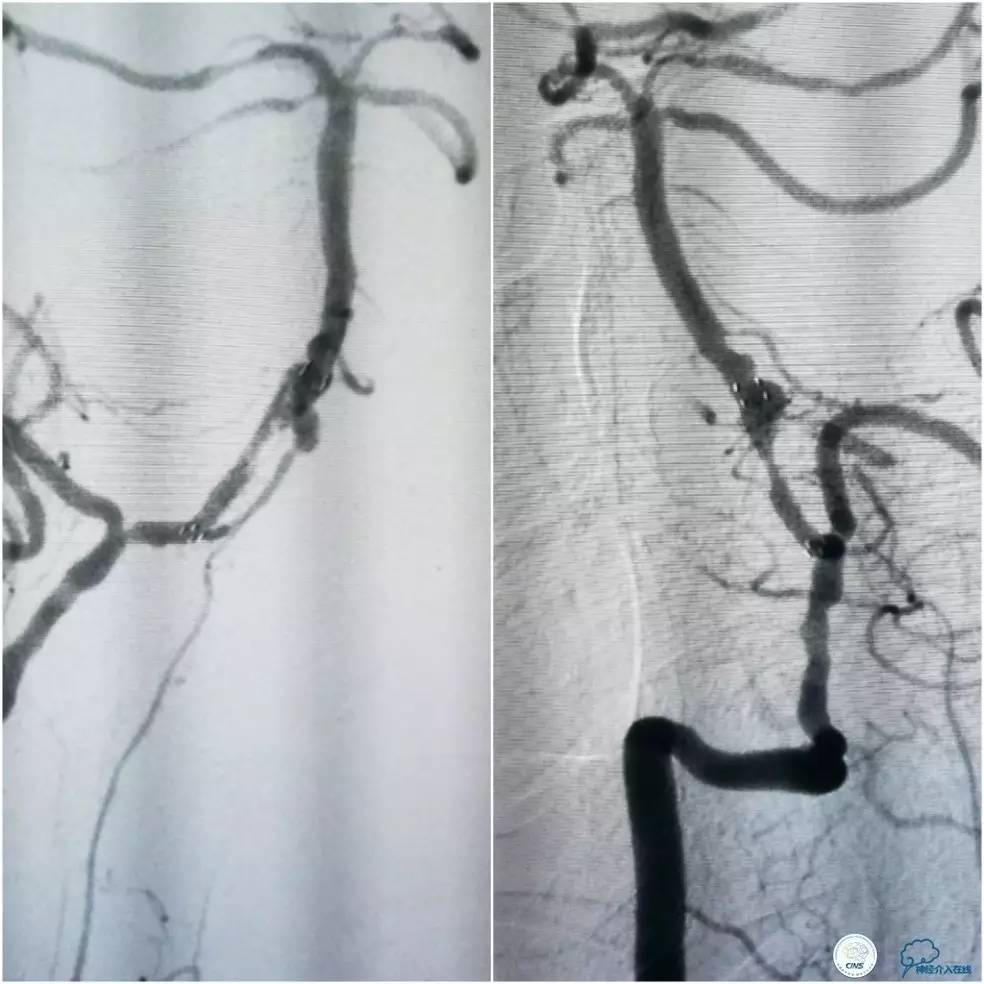

此时多体外投照显示右椎V4-基底动脉极重度狭窄,几近闭塞(图12)。

图12

Transend(0.014″300cm)微导丝+Echelon-10微导管,谨慎通过右椎动脉V4段病变后置于右大脑后动脉P1段(图13)。

图13

Gateway球囊(1.5mm×15mm)于狭窄段扩张后放置Wingspan支架(2.5 mm×15mm),撤出微导丝后造影,局部狭窄率50%,支架内中远段见细小充盈缺损,考虑急性血栓形成,予以欣维宁5ml动脉内缓慢注射未见好转(图14)。

图14

遂再次将Transend微导丝送至右大脑后动脉P1段,使用Gateway球囊(2.0mm×15mm)于支架最狭窄处后扩张(图15)。

图15

其后造影显示支架贴壁良好,远端血管显影好,前向血流TICI3级(图16)。

图16